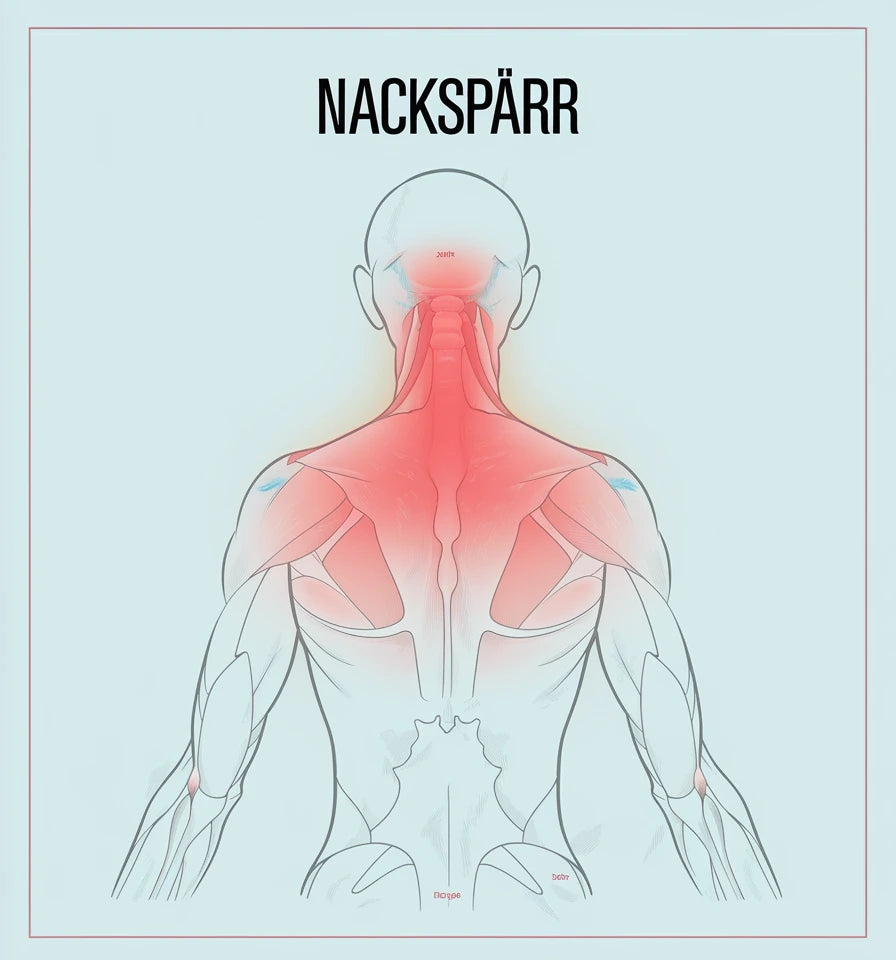

Nacken är en känslig och viktig del av kroppen som lätt drabbas av spänningar, överbelastning eller skador. Vanliga besvär inkluderar nackspärr, whiplash och nervinklämning. Vi guidar dig genom vanliga symtom och vad du kan göra åt dem.